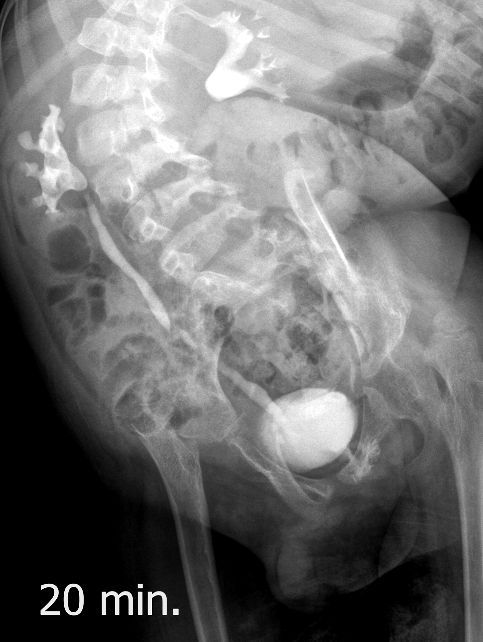

Поскольку откликов нет, добавляю экскреторные урограммы этого же пациента

Нейрогенный мочевой пузырь (?), МКБ, конкремент мочевого пузыря, двухсторонний мегауретер, конкремент правой почки.

И что законтрастировалось на экскреторных урограммах около мочевого пузыря?

Верификация:

Выдержка из протокола операции- "...вскрыт мочевой пузырь, обнаружен камень 4 х 3х 2.5 см, плотный, удалён. При дальнейшей ревизии мочевого пузыря обнаружен вколоченный камень в шейке мочевого пузыря и в уретре, удалён камень 2 х 1.5 х 1.5 см. При осмотре устья левого мочеточника - последний зияет, мочеточник расширен до 1 см, учитывая расширение мочеточника, проведена антирефлюксная пластика по Грегуару..."

На экскреторной урограмме - размеры собирательной системы левой почки уменьшились. Визуализирована расшиенная контрастированная проксимальная уретра.